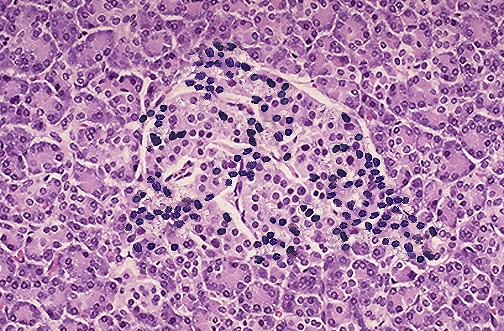

A diseased Langerhan cell exhibiting insulitis.  The black dots are lymphocytes that have

invaded the lysed cell (Chase 1999).